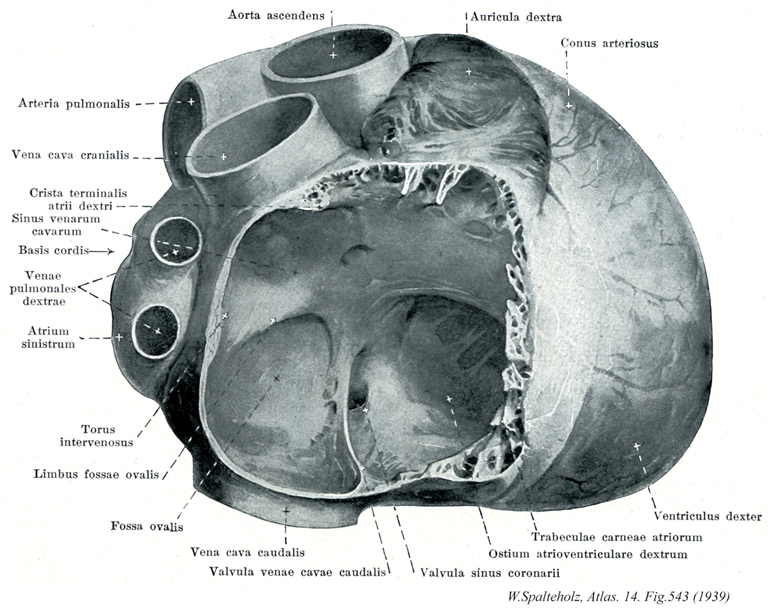

543

- 543_01【Ascending aorta上行大動脈;大動脈上行部 Pars ascendens aortae; Aorta ascendens】 Ascending part of the aorta up to its exit from the pericardium.

- 543_02【Pulmonary trunk; Pulmonary artery肺動脈幹;肺動脈 Truncus pulmonalis; Arteria pulmonarlis】 Arterial trunk that ascends in the pericardium. It divides into the right and left pulmonary arteries at the level of the reflection of the serous pericardium.

- 543_03【Superior vena cava上大静脈 Vena cava superior; Vena cava cranialis】

- 543_04【Crista terminalis of right atrium; Terminal crest of right atrium分界稜(右心房の) Crista terminalis atrii dextri】 Muscular ridge extending from the opening of the superior vena cava anteriorly over the lateral wall of the atrium to the lateral side of the opening of inferior vena cava. Inner border between the atrium and sinus venosus, which is present during embryonic development.

- 543_05【Sinus of venae cavae大静脈洞 Sinus venarum cavarum】 Smooth-walled space bounded by the crista terminalis for the passage of blood from the inferior and superior venae cavae.

- 543_06【Base of heart心底 Basis cordis】 Broad aspect of the heart facing dorsally and to the right, located opposite to the apex of the nearly conical heart, it is mainly formed by the posterior wall of the left atrium. The pulmonary arteries and vasa privata arise and open here.

- 543_07【Right pulmonary veins右肺静脈 Venae pulmonales dextrae】 The two right pulmonary veins which occasionally unite to form a single trunk.

- 543_08【Left atrium左心房 Atrium cordis sinistrum; Atrium sinistrum】

Lower's tubercle

- 543_09Lower's tubercle【Intervenous tubercle静脈間隆起 Tuberculum intervenosum; Torus intervenosus】 Prominence on the posterior wall of the right atrium between the openings of inferior and superior venae cavae.

- 543_10【Limbus fossae ovalis; Border of oval fossa卵円窩縁 Limbus fossae ovalis】 Raised border around the fossa ovalis.

- 543_11【Fossa ovalis; Oval fossa卵円窩 Fossa ovalis】 Depression in the interatrial septum, which represents the closed foramen ovale (open during fetal development).

- 543_12【Inferior vena cava下大静脈 Vena cava inferior; Vena cava caudalis】 It arises at the union of the right and left common iliac veins, lies on the right side of the aorta, and opens into the right atrium of the heart.

Eustachian valve

- 543_13Eustachian valve【Valve of inferior vena cava下大静脈弁 Valvula venae cavae inferioris】 Semilunar fold in front of the opening of inferior vena cava. During fetal development it directs blood toward the foramen ovale.

- 543_14【Right auricle of atrium右心耳 Auricula atrii dextra; Auricula dextra cordis】 Outpouching of the right atrium.

- 543_15【Conus arteriosus; Infundibulum of right ventricle動脈円錐;漏斗(右心室の) Conus arteriosus; Infundibulum】 Funnelshaped smooth-walled outflow tract leading to the pulmonary trunk.

- 543_16【Left ventricle左心室 Ventriculus sinister】

- 543_17【Trabeculae carneae of atrium肉柱(心房の) Trabeculae carneae atriorum cordis】

- 543_18【Right atrioventricular orifice; Right atrioventricular opening右房室口 Ostium atrioventriculare dextrum】 Openings between the atria and ventricles.

Thebesian valve

- 543_19Thebesian valve【Valve of coronary sinus冠状静脈弁;冠状静脈洞弁 Valvula sinus coronarii】 Semilunar fold in front of the opening of coronary sinus.